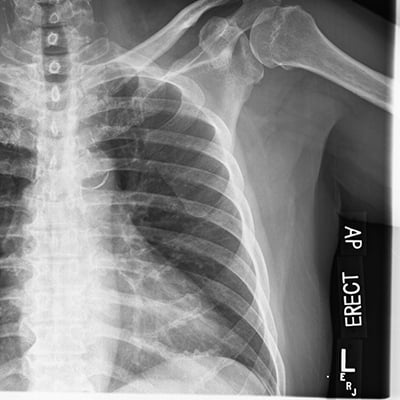

This module will help you achieve optimal images of the chest and abdomen, including AP and lateral decubitus chest examinations, and supine, upright, and decubitus abdomen examinations are also covered. Patient positioning, technical settings, and patient instructions are discussed. Descriptions and images of the expected anatomical structures are included, as well as image evaluation criteria.

This module will help you achieve optimal images when performing elbow, humerus, shoulder, and scapula examinations. Patient preparation and positioning are discussed, as well as technical settings and patient instructions. Descriptions and images of the expected anatomical structures are included, as well as image evaluation criteria.